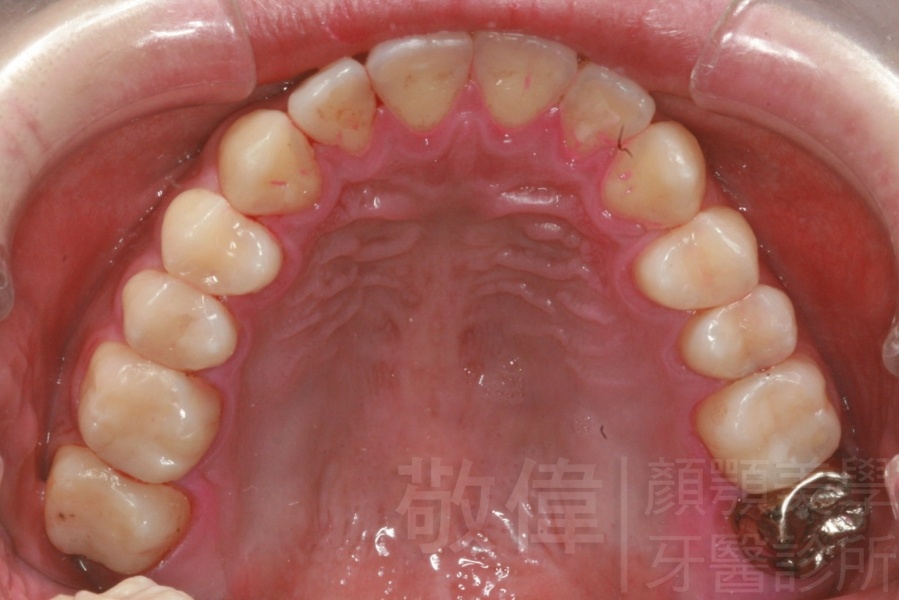

矯正前-上   矯正前-下

矯正後-上   矯正後-下

齒顏矯正/上顎暴牙且牙齒極度混亂

上顎暴牙且牙齒極度混亂,經由矯正之後,臉型大幅度改善,牙齒的排列更加的整齊健康。相較於之前眼神充滿精神,自信心展現無遺。